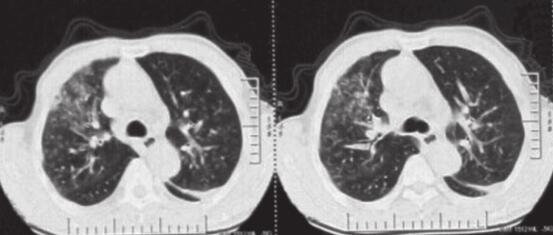

患者,刘某,男,66岁。因“反复咳嗽、咳痰2年余,再发加重3天”于2014年3月7日入院。自2012年以来,患者无明显诱因出现反复咳嗽、咳痰,多为白色泡沫痰,咳嗽剧烈时伴胸闷、气喘不适,间断高热,多次在外院住院治疗,每经抗感染及止咳祛痰等对症治疗后病情可缓解,出院后患者咳嗽、咳痰症状仍反复。自2012年起病以来,患者多次行肺部CT(图1~图4)检查提示“左下肺大片状及右上叶片状阴影”,行抗感染治疗后右肺上叶稍吸收,左下肺片状影吸收欠佳。2013年8月考虑患者“肺结核”不能排除,在本市结核病医院,查T-spot(+),后给予三联抗结核(异烟肼+利福平+乙胺丁醇)治疗2个月,咳嗽、咳痰未见明显好转。2013年11月曾因咳嗽、咳痰加重入我科,给予抗感染(左氧氟沙星)及继续抗结核(异烟肼+利福平+乙胺丁醇)治疗,期间患者因大便潜血(+)行肠镜检查,提示“乙状结肠直肠新生物”,病理检查示“乙状结肠腺癌”,于2013年12月8日转普外科行“乙状结肠癌根治术”。此次入院前3天,患者受凉后再发咳嗽,咳白色泡沫痰,量较多,偶为粉红色泡沫痰,咳嗽剧烈时感憋气、胸痛,无畏寒、发热,无恶心、呕吐,无双下肢水肿等不适。

图4 2013年12月17日肺部CT